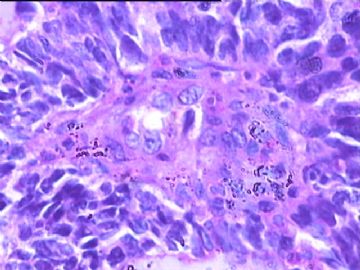

女,34y,头痛一月,右额叶占位:5*5*4cm。囊性区域,4cm。大体:3.5x3x1cm灰白间暗褐色组织一堆,质嫩。临床诊断1:胶质瘤,2:血管母细胞瘤。

本人县级医院头颅手术少,考虑胶质母细胞瘤。大家指导指导。

胶母

同意胶质母细胞瘤。细胞异型、坏死、核分裂、血管内皮肿胀增生均可见到。

This is certainly a WHO grade IV malignant neoplasm. While most likely a glioblastoma, I would carefully rule out PNET by staining for GFAP and neuronal markers such as synaptophysin, NeuN and NSE. Rarely, PNET may shows marked pleomorphism and indistinguishable from glioblastoma on HE stain.

同意马老师的意见,该肿瘤从形态及年龄来看考虑PNET或GBM,须标记Syn、NSE、S-100、NeuN和GFAP来鉴别。

结合图片细胞形态特点考虑胶质母细胞瘤,组化标记排除其他